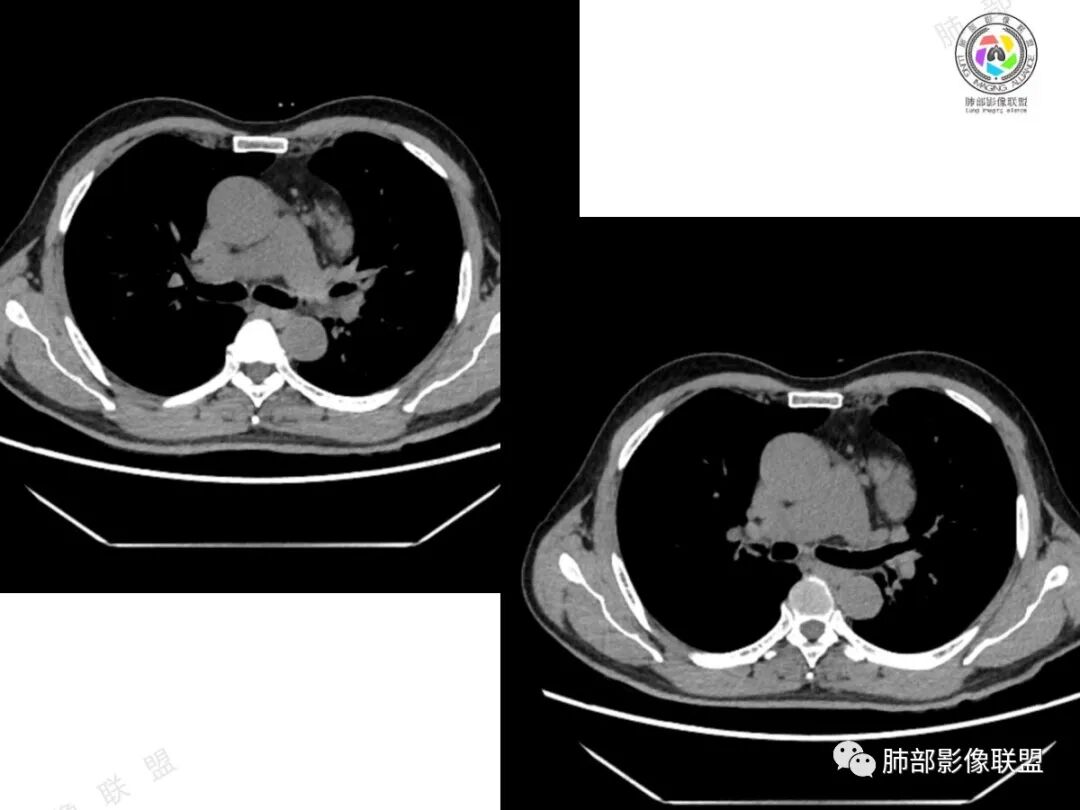

2、影像所见:左侧纵隔紧贴心包铸型生长巨大混杂密度肿块,边界清楚,临近结构受推挤移位,无明显外侵征象。肿块自主动脉弓旁一直顺延到至膈顶,呈“垂乳征”。病灶脂肪成分居多,斑片状、结节状及团块状实性密度成分散落其中,呈地图样分布,实性成分偶见低密度线样分隔,未见明确钙化影。增强扫描实性成分呈延迟明显强化,并见强化血管影。纵隔内有肿大淋巴结,未见胸腔积液,肺内及胸膜未见转移性病灶。

3、影像诊断:脂肪肉瘤?胸腺脂肪瘤?畸胎瘤?胸腺瘤?

④胸腺瘤:常见于40岁以上患者,是最常见的前纵隔肿瘤,大多数位于前纵隔,其次为心包旁,常偏侧生长,多数密度均匀,大于15㎝罕见,一般轻-中度强化,少数可明显强化。黄勇老师认为,胸腺瘤病理标本上均伴有不同程度间隔存在,随着侵袭性增强,分隔会逐渐不显著。当病灶有明确分隔,较均匀强化时,胸腺瘤一定要考虑到。